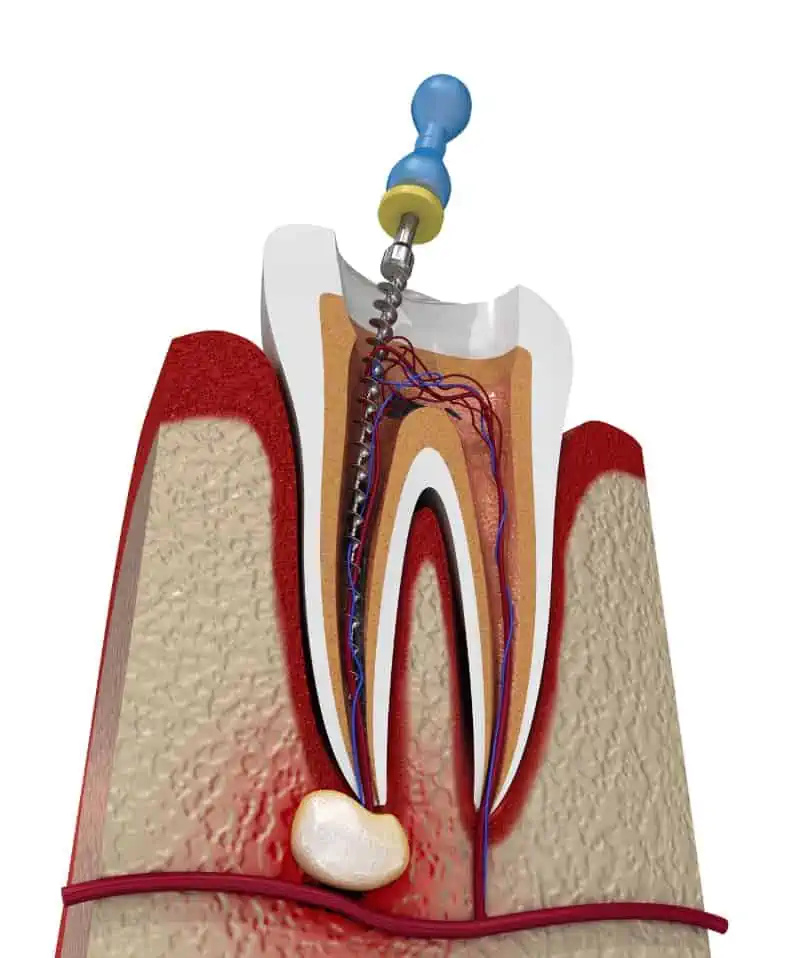

Dental pain can disrupt your daily routine and affect your overall health. At Smilescape Dental Care in Tiruvallur, Chennai, we provide specialized root canal treatments designed to relieve pain, save your natural teeth, and restore full dental function. With modern technology, skilled endodontists, and patient-focused care, our clinic has become a leading choice for root […]